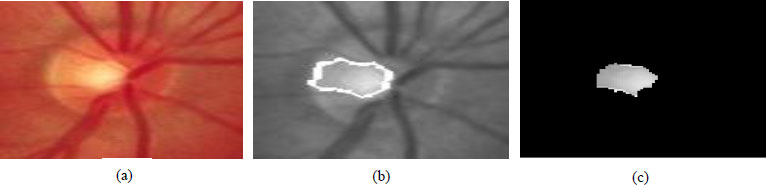

Three different segmentation techniques, such as the Gradient-based active contour method, Level set, and K-means clustering-based segmentation method, are proposed for the extraction of optic disc and optic cup. The retinal pictures have been taken in an RGB mode by a fundus camera. A sample image taken for analysis is given in Fig. (10). The assessed area around the distinguished, most splendid point is to be chosen for the introductory optic circle district as ROI. After investigating the whole assortment of fundus pictures, a square of size 360x360 pixels with the most splendid pixel as the middle point is chosen to consider as ROI.

The calculation holds the shape component of the ideal plate, and its exhibition depends on the form statement. The fundamental point of the strategy is to limit the energy capability displayed in condition (1), as presented in Eq. (11). The underlying form focuses on physically restricting the limit of optic plate locale. The optic circle locale is sectioned from the pre-handled dark scale picture displayed in Fig. (11). ChanVese (CV) model is additionally a functioning form model. The model is additionally reclassified to separate the OD locale from the comparable trademark districts around it by coordinating data from the various pictures, including channels.

Fig. (10). Results of active contour technique, (a) Original fundus image, (b) Initialisation of contour, (c) Segmented optic disc.

Level set techniques are utilized for performing shape advancement. The capability φ (I, j, t) (level set capability) is characterized where (I, j) are arranged in the picture plane and t addresses 'time'. At any coordinated time, the level set capability simultaneously characterizes an edge form and a division of the picture. The edge form is taken to be the zero-level set {(i, j) s. t. φ (I, j, t) = 0}, and the division is by the two districts {φ≥0} and {φ<0} [48]. The level set capability will be advanced by some incomplete differential condition. If the forefront is characterized to be in the locale where φ< 0, then the foundation found by this division would be the area inside the circle. Fig. (12) shows the results of optic cup segmentation using the level set method.

Fig. (11). Results of level set technique, (a) Original fundus image, (b) Cup boundary, (c) Segmented cup region.